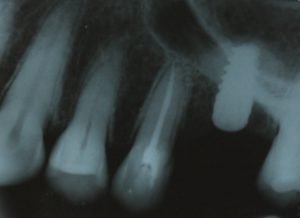

Figura 7: rx pós-operatório mostrando a membrana levantada pelo biomaterial.